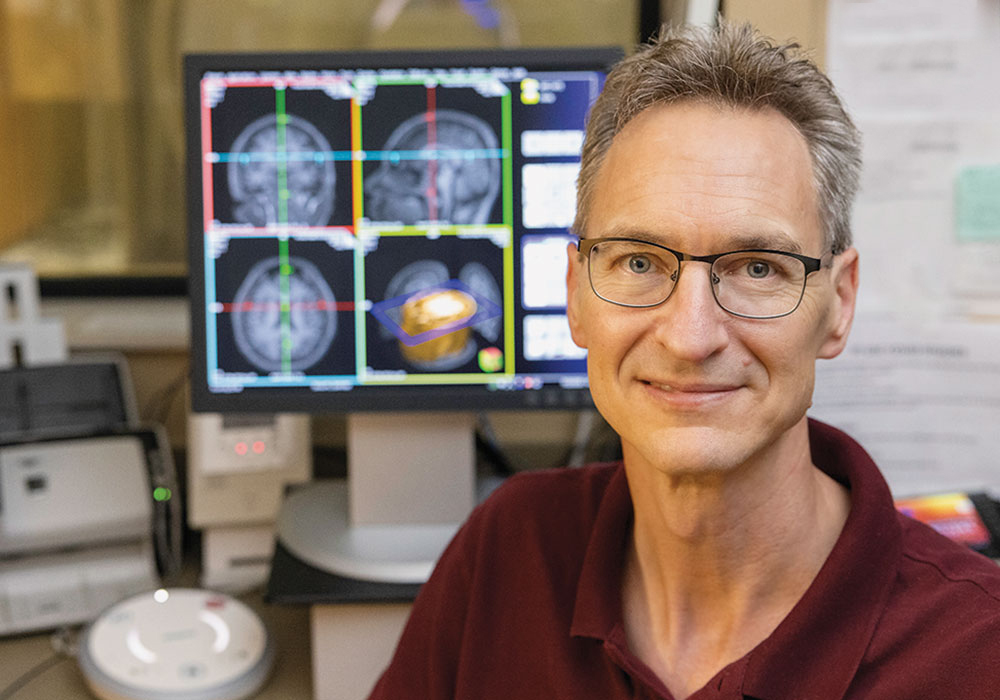

When the MRI hit the scene, it meant big things for clinical care — and for research. Just ask psychology professor Chris Rorden, whose Endowed Chair of Neuroimaging is funded by USC benefactor Peter McCausland. Rorden is co-director of USC’s McCausland Brain Imaging Center, home to the equipment used to scan Marcus Ryninger and thousands of other study participants since 2006.

MRIs are commonplace in hospitals today, but most have a magnetic field strength of 1.5 Teslas or less. The McCausland Center’s scanner is a 3 Tesla, twice the strength of typical MRIs.

Then there’s the appeal to prospective students and faculty. Rorden himself was drawn to USC by the scanner. The researcher, who earned his Ph.D. from Cambridge, developed the free neuroimaging visualization software that’s used by scientists around the world.